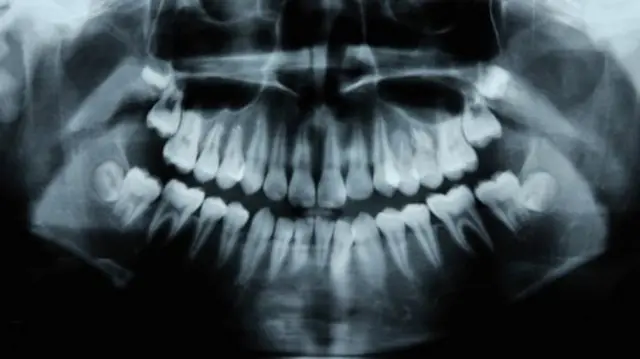

Periodontitis, au ugonjwa wa ufizi, ni ugonjwa wa pili unaoenea zaidi wa kinywa baada ya kuoza kwa meno unaoathiri zaidi ya 47% ya watu wazima wenye zaidi ya umri wa miaka 30.

Kuanzia umri wa miaka 65, 64% wana periodontitis ya wastani au kali. Ulimwenguni ni ugonjwa wa kumi na moja unaojulikana zaidi ulimwenguni.

Periodontitis ni ugonjwa ambao haupatikani juu ya ufizi ambao unaweza kuona unapotabasamu, lakini hukaa chini kabisa.

Baada ya awamu ya awali ya uvimbe wa juu juu katika sehemu inayoonekana ya ufizi (gingivitis), bakteria husafiri chini ya mstari wa fizi hadi kwenye mifuko iliyo karibu na mzizi wa jino ambapo humomonyoa miundo inayoshikilia jino.

Kutokana na hali ya kujificha ya ugonjwa wa periodontitis, wagonjwa wengi hawajui kuwa iko pale hadi utakapofika hatua za mbele zaidi ambapo huchangiwa na usafi wa mdomo pia.